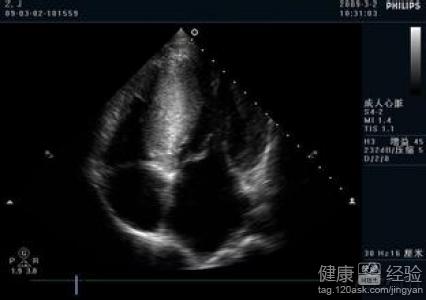

我父親今年已經有六十一歲了,在二十年前的時候,我父親就患有了高血壓的疾病,這些年我父親也有斷斷續續的吃藥進行治療,但是最近一段時間,我父親總是感覺到胸悶,而且人也感覺特別疲憊,有的時候一整天都是昏昏沉沉的沒有精神,到醫院檢查後,竟然發現患有的是肥厚性非梗阻性心肌病,那到底像我父親這樣的情況,采取中藥應當要如何治療呢?

1該病的發展通常較為緩慢,所以一旦患者發病後沒有及時的進行治療,很容易出現了心律失常或者是猝死的情況發生,建議患者可以使用中藥的:人參10克,甘草10克,干姜8克,寸冬10克,五味子8克,桂枝12克,當歸12克,桃仁10克,進行治療。